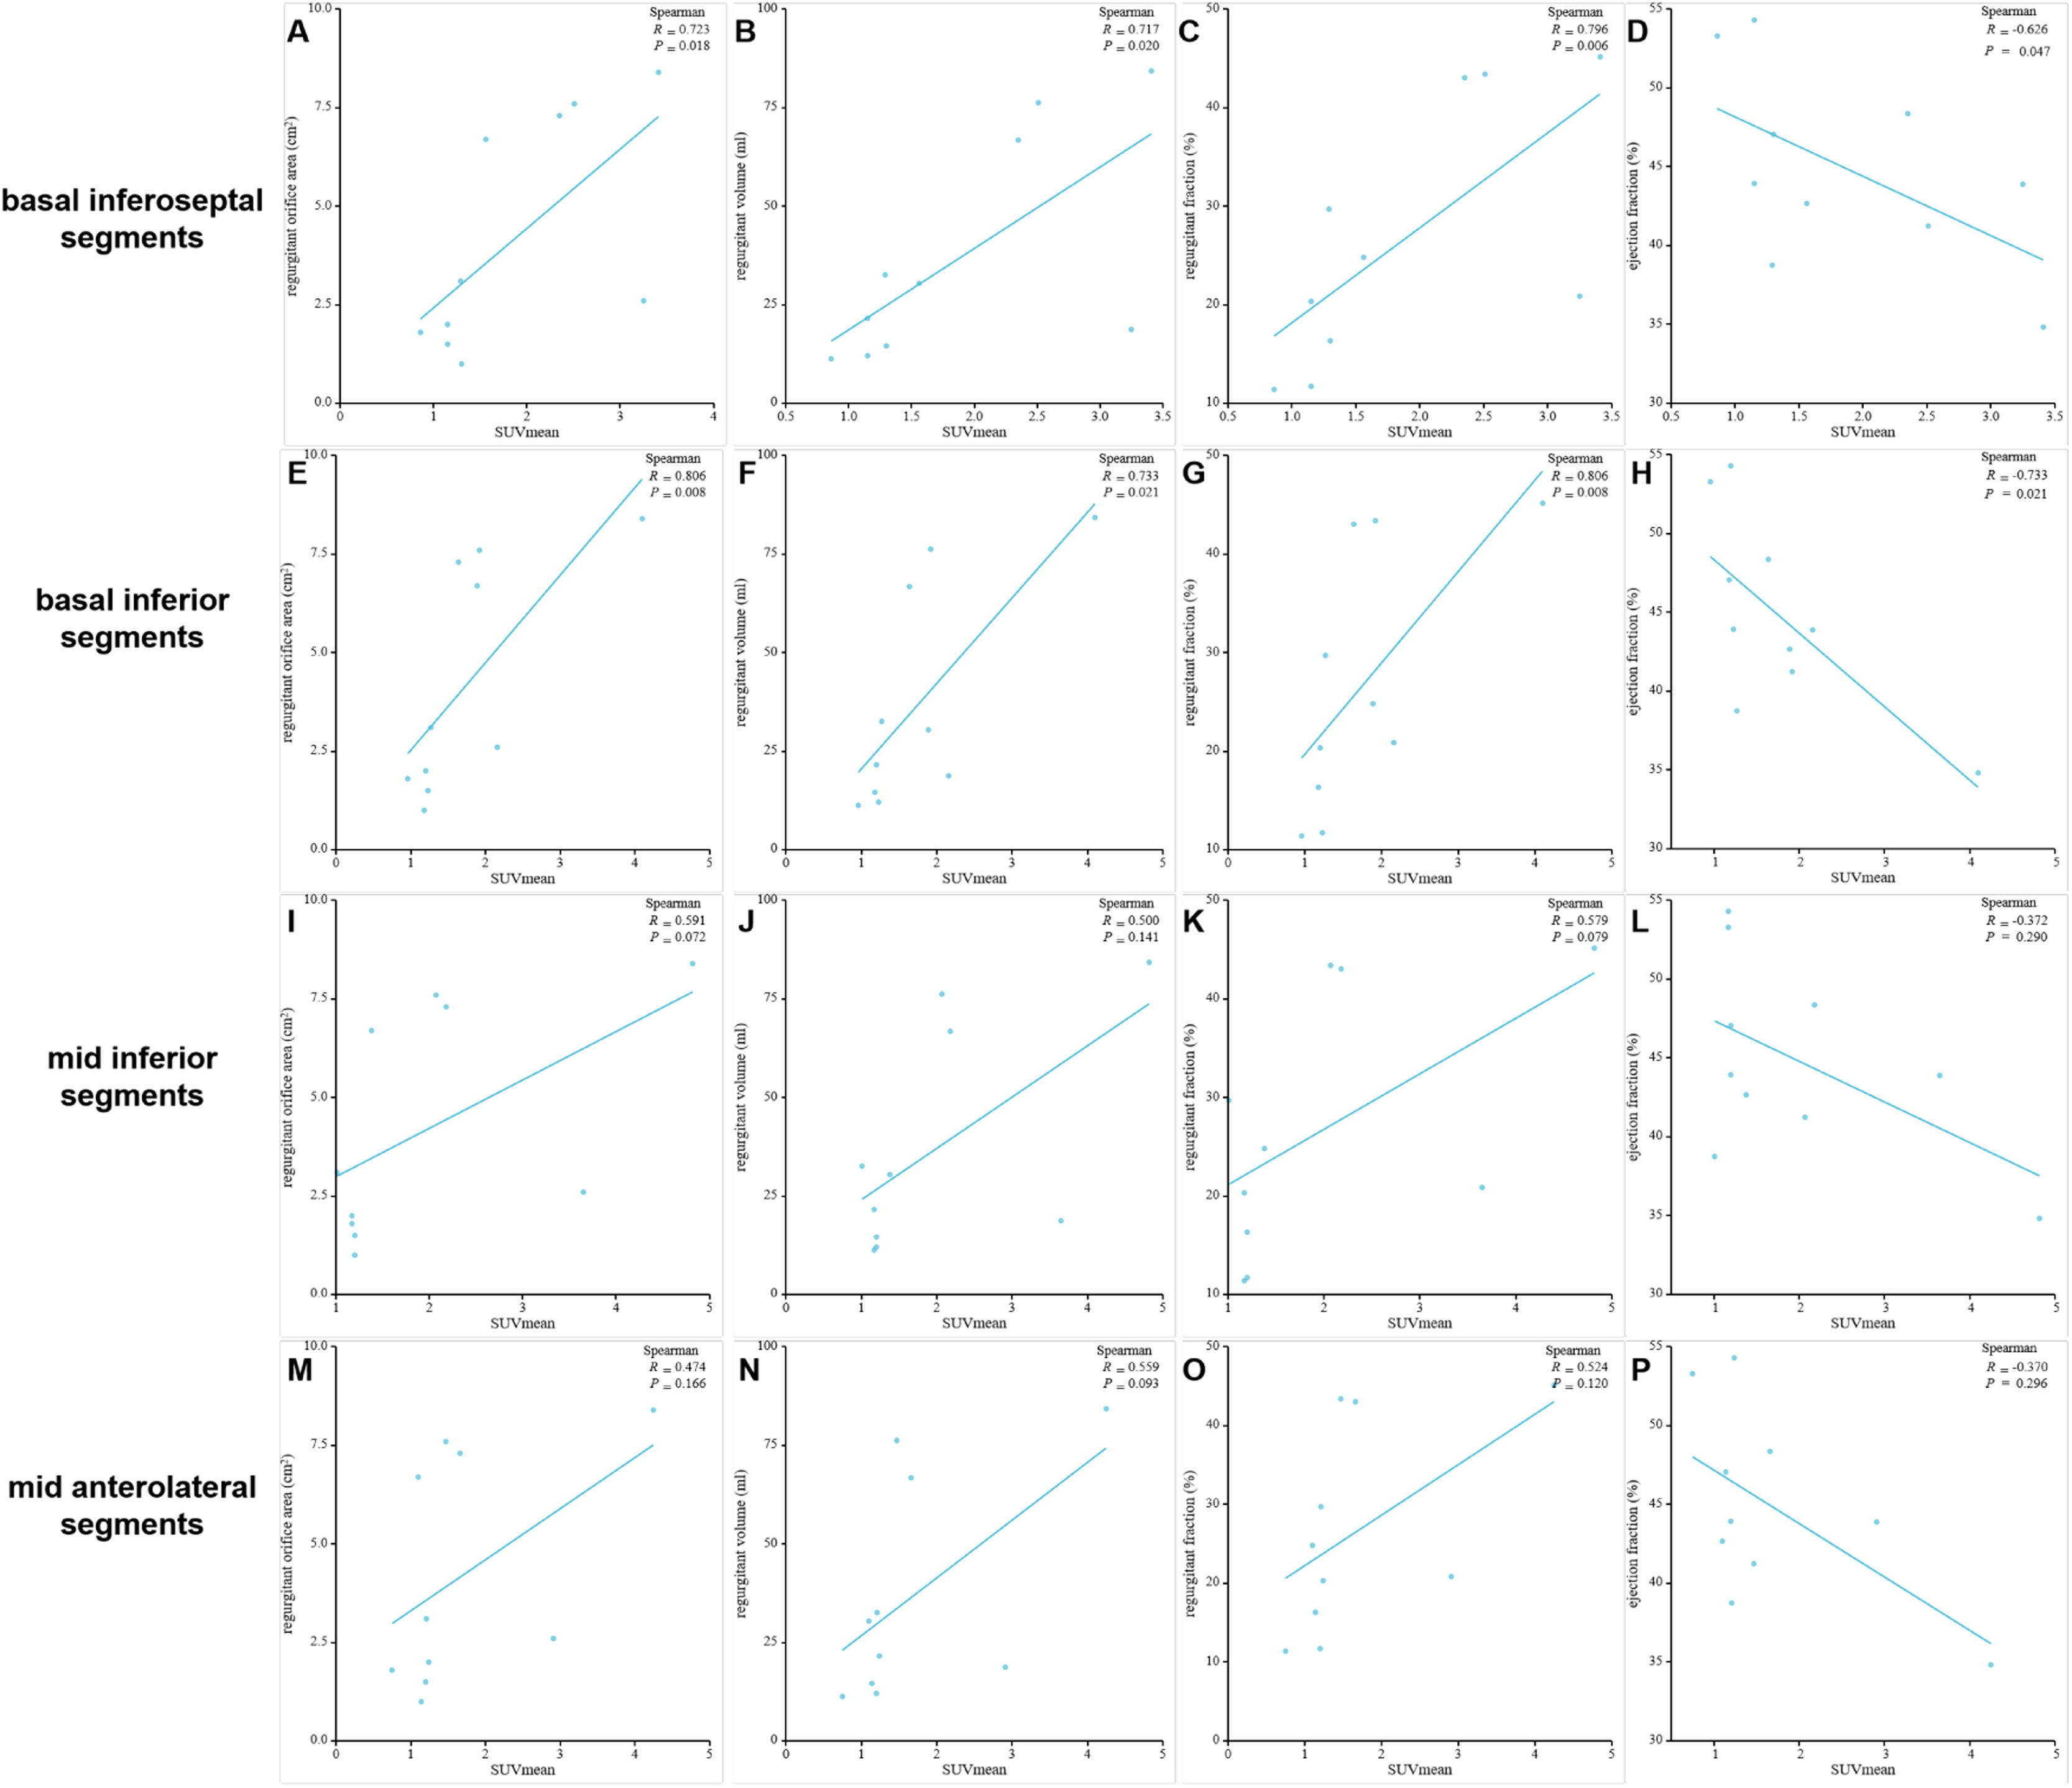

Correlation of SUVmean in the myocardial segments of high FAPI uptake with MVR parametersPositive correlations were observed between SUVmean of FAPI and regurgitant volume, regurgitant fraction, and regurgitant orifice area in the basal inferoseptal and basal inferior segments. Conversely, a negative correlation was observed between SUVmean of FAPI and ejection fraction within these segments. These results were as follows: r = 0.723, p = 0.018 and r = 0.806, p = 0.008 for regurgitant orifice area in the basal inferoseptal and basal inferior segments; r = 0.717, p = 0.020 and r = 0.733, p = 0.021 for regurgitant volume in the basal inferoseptal and basal inferior segments; r = 0.796, p = 0.006 and r = 0.806, p = 0.008 for regurgitant fraction in the basal inferoseptal and basal inferior segments; and r = -0.626, p = 0.047, and r = -0.733, p = 0.021 for ejection fraction in the basal inferoseptal and basal inferior segments (Fig. 6A‒H and Table 3). However, the SUVmean of FAPI in the mid-inferior and mid-anterolateral segments was not significantly correlated with these parameters of mitral regurgitation (all p < 0.05; Fig. 6I‒P).

The European and American guidelines for the definition of severe mitral regurgitation use regurgitant orifice area, regurgitant volume, and regurgitant fraction for quantification and risk stratification.24,25 However, their clinical utility is limited.26 Given the intrinsic relationship between the basal inferoseptal, basal inferior, mid inferior and mid anterolateral myocardial segments and the anatomic locations of papillary muscles and valve annulus and their increased susceptibility to fibrosis in mitral regurgitation, the correlations between these parameters and SUVmean of FAPI in these myocardial segments were analyzed. Notably, FAPI uptake and regurgitant volume, regurgitant fraction, regurgitant orifice area and ejection fraction demonstrated strong correlations in the basal inferoseptal and basal inferior segments These findings indicate that myocardial fibrosis in these two segments could directly impact mitral valve function. Notably, FAPI uptake in the basal inferoseptal and basal inferior segments serves as a potential surrogate marker for additional risk stratification and regurgitation quantification in degenerative mitral regurgitation.